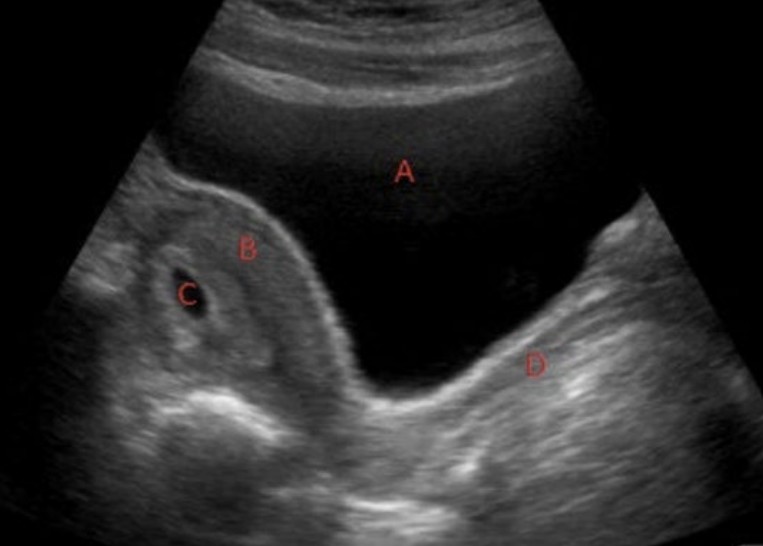

A 24-year-old woman presents with abdominal pain and vaginal bleeding. Her last menstrual period was eight weeks ago and pregnancy status is unknown.

Her bHCG level returns at 7400IU/L.

3. Identify the labelled structures on the ultrasound image. 4 marks

Question image